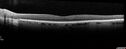

Advanced age-related macular degeneration219 views87 year old female. Severe macular bleed 15 years ago OD. Now with disciform scar. Left eye has progressing geographic atrophy.

VA OD: HM, OS: 5/200. IOP normal OUMar 17, 2024